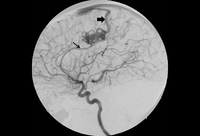

Cerebral angiogram (left carotid artery injection, lateral view) showing posterior frontal arteriovenous malformation fed by pericallosal artery (thin arrow) with arterialised draining vein (thick arrow) draining to superior sagittal sinus

From the collection of Mr R. J. Edwards; used with permission